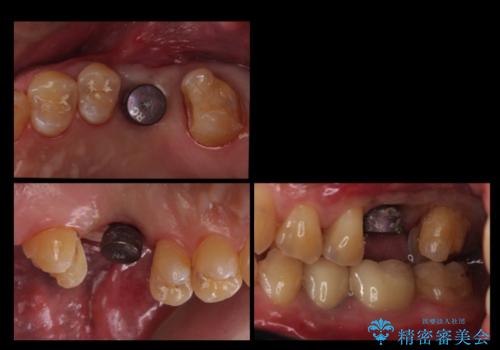

- 上の奥歯が無いところにインプラントを希望して来院。

インプラントの向かい合わせの歯や隣の歯の虫歯治療も併せて行なっています。

同時期に治療することで咬み合わせの調整がしやすく、また、適合の良いものを作成できるメリットがあります。